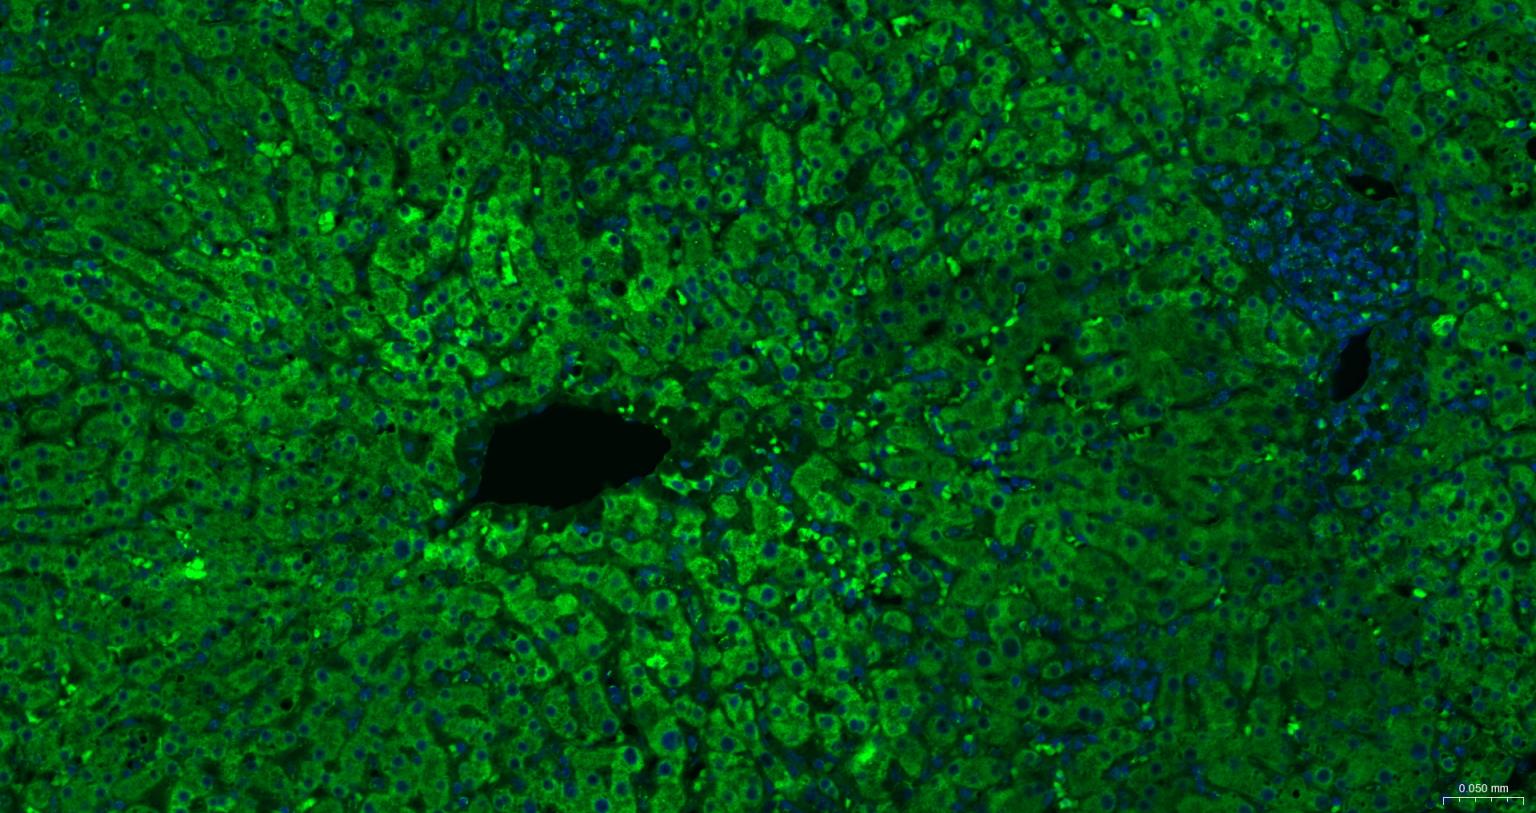

Paraformaldehyde-fixed, paraffin embedded Human Liver; Antigen retrieval by boiling in sodium citrate buffer (pH6.0) for 15 min; The section was incubated with COX4I1 Monoclonal Antibody, Unconjugated (bsm-52750R) at 1:200 overnight at 4°C. Followed by conjugated Goat Anti-Rabbit IgG antibody (Green, bs-0295G-BF488), DAPI (blue, C02-04002) was used to stain the cell nuclei.